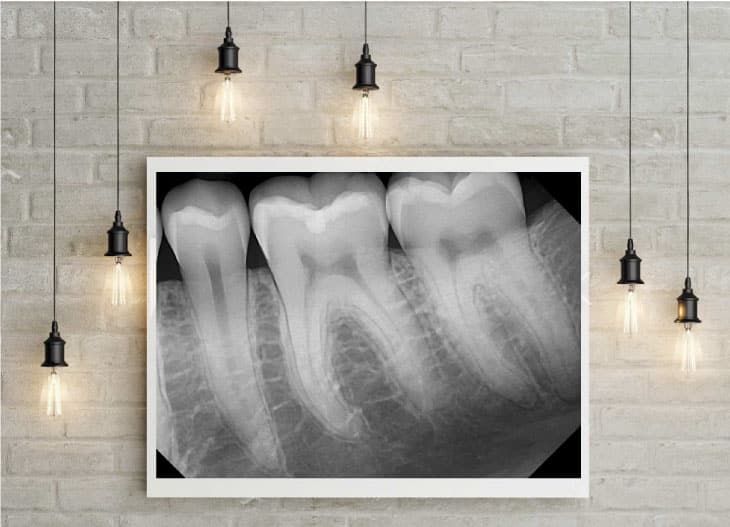

Ramey took an X-ray of Arnett and a few seconds later, Christensen, a renowned prosthodontist, exclaimed, "Nice image!" according to Ramey. The group of experts stood up from their seats and gathered around Christensen, eager to examine the image on his laptop. Ramey recalls this moment with great pride.

"Over time, this secret sauce that he came up with, just the right exposure rates, the right settings, the filters, the software, and just the right combination, he was able to produce these beautiful images," Arnett said.

"I did a lot of work getting the image looking just right, which is kind of art. I do see it as an art form, more than something technical," Ramey said.

Just as people used to turn the radio dial to hear the music without any static or noise on analog radios, Ramey said he "dials in" the image that they capture with DentiMax sensors by finding the optimal exposure settings on the X-ray heads to get the best raw image possible. Then he applies the best filters, enhancements, and algorithms to get the perfect image according to each doctor’s preferences.

"No one else does that," Ramey said. "They have different algorithms in their software that try to optimize the energy that hits the sensor and make the best image they can with it. I do it the opposite way. I find the optimal amount of energy first, get the best raw image I can, and then I make it look good," he added.

"A good-quality image will stay in most patients’ minds and motivate them to schedule needed treatment," Dr. Kent Stapley said. "Not only do patients want a proper diagnosis and early by their dentist, but many of them would also like to see for themselves what is wrong with their teeth."